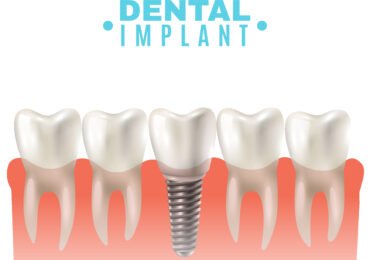

زراعة الأسنان

زراعة الأسنان هي الحل المثالي

لتعويض الأسنان المفقودة واستعادة الابتسامة والثقة.

نستخدم أفضل أنواع الزرعات، وننصح بالزرعات الألمانية لجودتها العالية.

تتم الزراعة بتخدير موضعي وبدون ألم، وغالباً تكون فورية في نفس اليوم.

ولله الحمد، أغلب مرضانا يشعرون براحة تامة أثناء العملية.